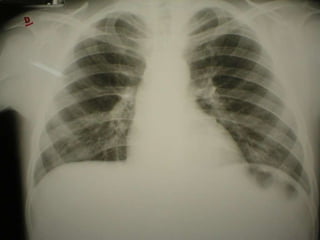

11/08/2003- p=48kg,PA=140x60 mmHg, diurese=940mL/dia Hemácias 5.760.000/mm 3 Hb 16,9g% Htc 49,5% Leucócitos 8.700/mm 3 S 69 L 25 M 6 Plaquetas 436.000 Uréia 66 mg/dl Creatinina 0,6 mg/dl K 4,7 Albumina=1,5 PCR <6mg/dl Atividade de Protrombina: 65% RNI 1,16 PTTa p=37/c=29 – relação=1,28 12/08/2003- p=48kg, PA= 120x80mmHg, diurese=820mL/dia 13/08/2003- p=48kg, PA= 130x60mmHg, diurese=1650mL/dia 14/08/2003- p=47,7kg, PA= 120x70mmHg, diurese=1280mL/dia VHS = 46 mm/hora Creatinina 0,5 mg/dl Proteínas totais= 3.5 Albumina=1,5 Globulina=2,0 Relação A/G=0,75

15/08/2003- p=46,5kg,PA= 120x90mmHg, diurese=1880mL/dia 16/08/2003- p=45,5kg, PA= 110x60mmHg, diurese=1660mL/dia Hemácias 5.240.000/mm 3 Hb 15,6g% Htc 44,0% Leucócitos 10.900/mm 3 S 78 L 17 M 4 E 1 Plaquetas 369.000 K 4,0 Tempo de sangria= 1’ Atividade de Protrombina: 100% RNI 1,00 PTTa p=27/c=27 – relação=1,00 17/08/2003- p=44kg, PA= 116x70mmHg, diurese=2350mL/dia 14/08/2003 – exames liberados 1 dia após alta FAN: negativo Ac anti-neutrófilos P-ANCA: negativo Ac anti-neutrófilos C-ANCA: negativo